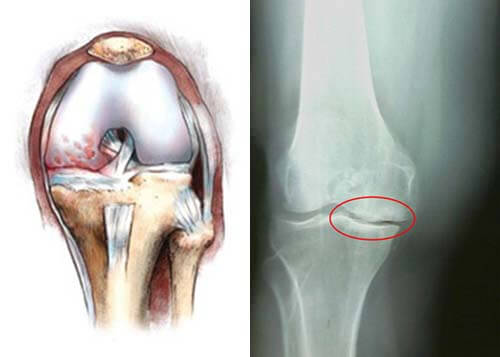

В коленном суставе имеется два вида хрящей. И когда говорят о повреждениях хряща коленного сустава, чаще всего подразумевается травма мениска – волокнистой ткани. Но не стоит забывать, что повреждаться способен и гиалиновый хрящ. Это особая ткань, которая покрывает мыщелки суставообразующих костей и надколенник с внутренней стороны.

Любые дистрофические изменения сопровождаются ссыханием, растрескиванием хрящевой ткани в колене. При этом он начинает стираться, растрескиваться. На фоне недостаточного питания хрящ может полностью стереться и оголить кость. На высохших и затвердевших хрящах начинают образовываться остеофиты. Это костные наросты в виде кристаллов кальция, которые в народе именуются как отложение солей.

Остеофиты и шипы, которые замещают упругую и амортизирующую ткань, и еще больше ее разрушает. При этом возможность противостоять нагрузкам стремительно уменьшается, а колено теряет свою функциональность.

Соответственно расстояние между костными элементами уменьшается, что проявляется скованностью в движениях, трением. При этом проблемы прогрессируют, появляется утренняя скованность, болезненная симптоматика, как в состоянии покоя, так и при нагрузках. Человеку тяжело передвигаться, что становится причиной прихрамывания. Это влечет за собой неправильные перераспределения нагрузок – страдают мышцы, позвоночник.